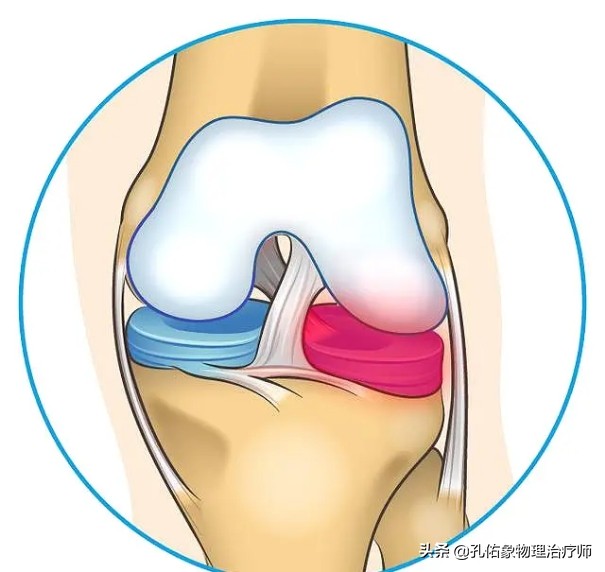

仅仅是在靠近膝关节的关节囊外层区域有一定的血供,临床上称此区域为红区;而在半月板最内层区域,是没有血液供应的,仅仅靠滑液来供应营养,临床上称此区域为白区,若是损伤了,基本不可能自愈;在红区与白区之间的这个范围,称为红白区,血液供应也不太多,自愈恢复相对较慢。对于老年人来说,因为自身的血液循环相对不好,若是出现半月板的白区及红白区的损伤,愈合能力就非常低。所以,半月板的损伤,一般都还是建议手术治疗。

这种手术方式往往适用于损伤部位在红区的患者,如上图中标记1和2的部位损伤者;由于这个区域的半月板有血供,都会选择半月板缝合的方式来让它自愈,为减少后期的并发症(如创伤性关节炎、活动时的卡顿等)埋下伏笔。

这种手术方式往往适用于损伤部位在红白区的患者,如上图中标记3和4的部位损伤者;由于这个区域的半月板虽然仍有部分血供,但是相对红区的愈合能力就大大的降低,所以一般会选择半月板的部分切除成型的方式来弥补半月板的形状,为减少后期的并发症(半月板的磨损)埋下伏笔。这个手术的特点就是把损伤撕裂的半月板切除,然后尽可能的恢复还原半月板的C型或O型的形态结构。